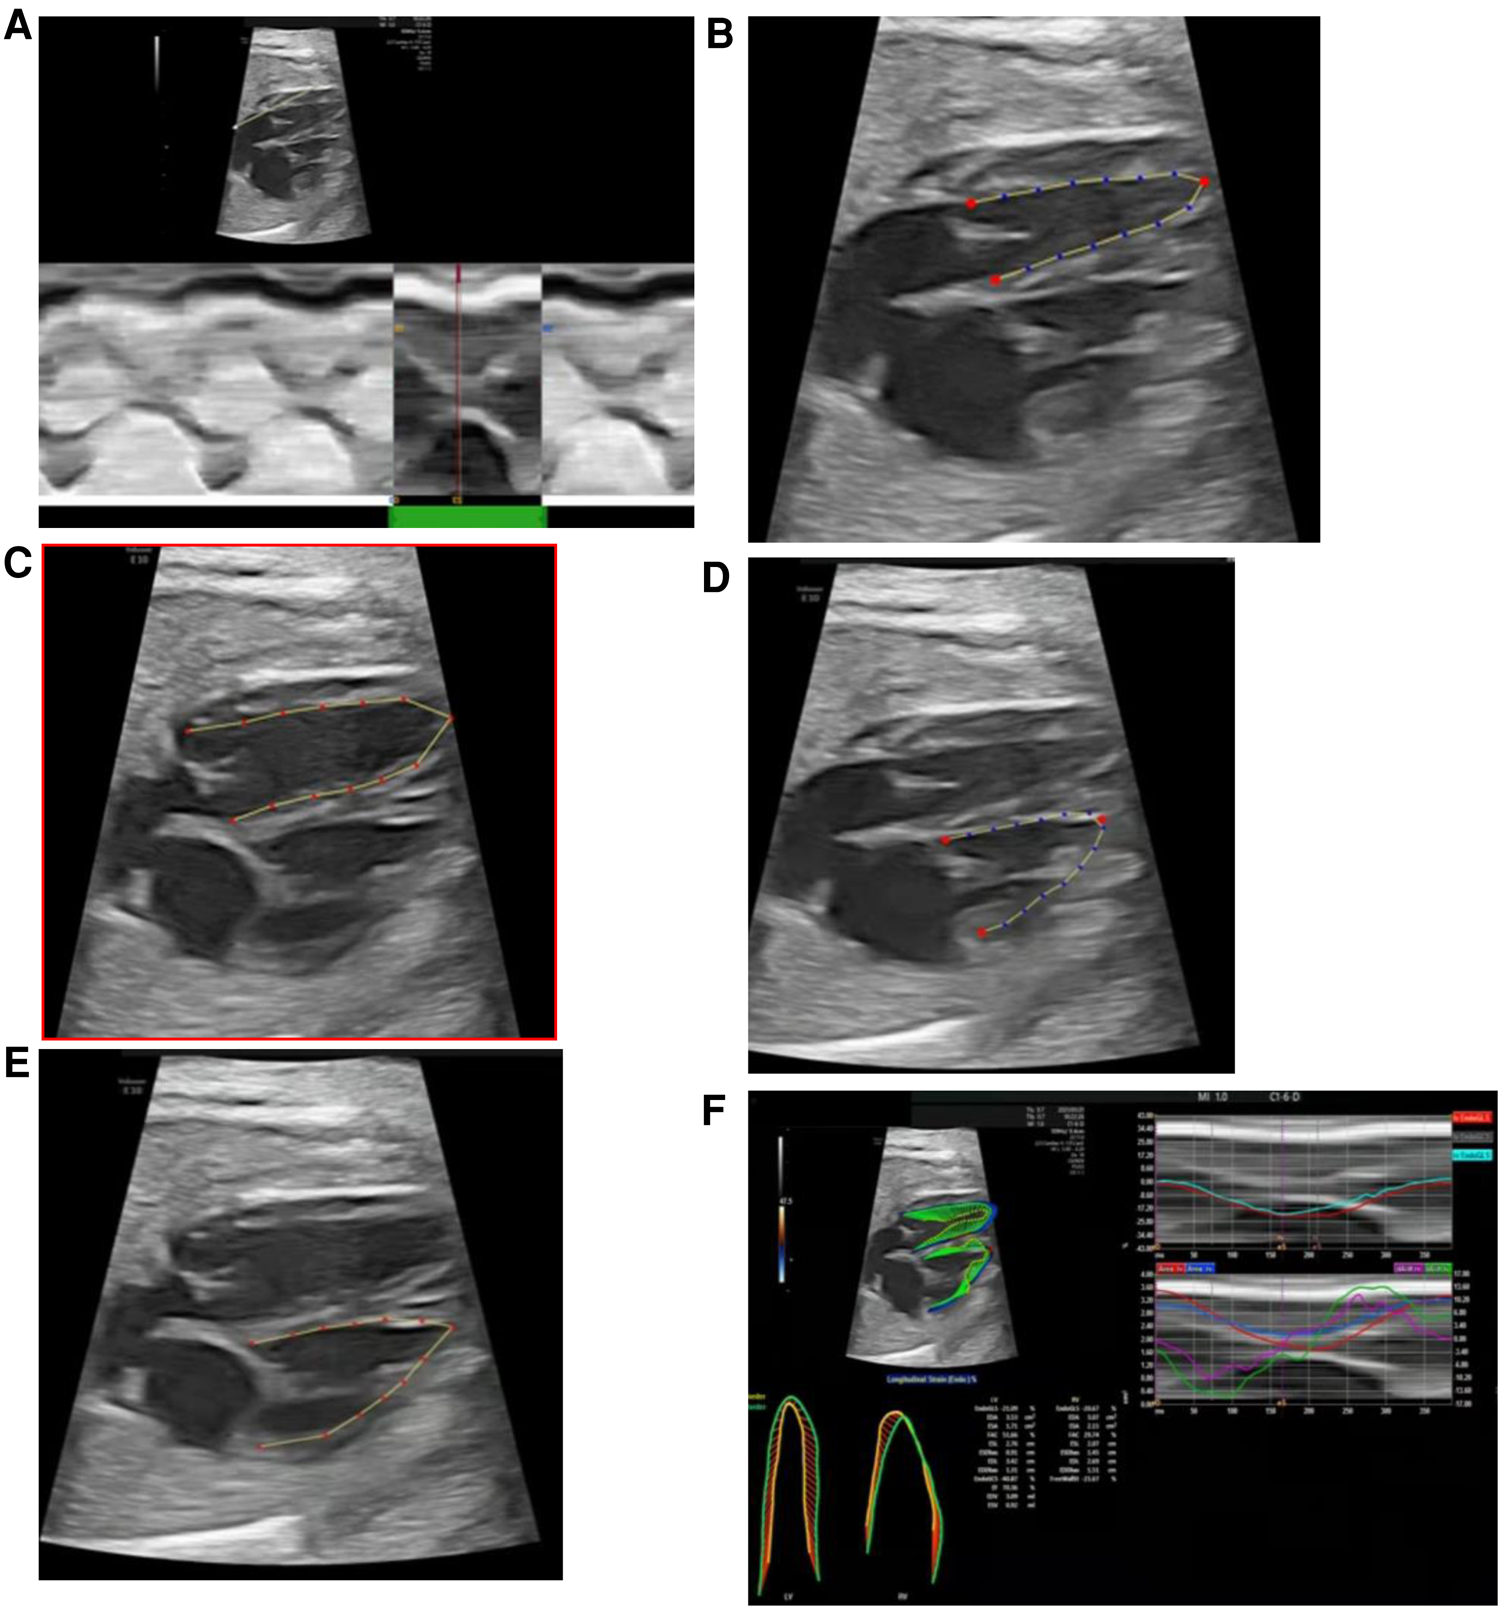

The fetalHQ speckle tracking software (build-in the Voluson E10 ultrasound system) measures ventricular parameters as follows: (1) the M-Mode line is drawn from the apex through the lateral base of the left ventricle (mitral valve lateral anulus), and one cardiac cycle is selected (Figure 2A); (2) left ventricular end-systolic endocardial tracing is defined, and the three red anchor points and blue dots can be adjusted (Figure 2B); (3) left ventricular end-diastolic endocardial tracing is defined, and the red dots can be adjusted (Figure 2C); (4) the endocardial border of the right ventricle at end-systole and end-diastole is traced sequentially (Figures 2D,E); and (5) measurements are completed, with the results exported and reported (Figure 2F).

Figure 2

fetalHQ speckle tracking software measures left and right ventricular parameters. (A) Selection of one cardiac cycle (M-Mode); (B) defining of left ventricular end-systolic endocardial tracing; (C) defining of left ventricular end-diastolic tracing; (D) defining of right ventricular end-systolic endocardial tracing; (E) defining of right ventricular end-diastolic tracing; (F) obtaining of results and report.